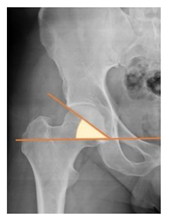

Plain radiographs were evaluated preoperatively and at the most recent follow-up, after appropriate calibration. Positional parameters were assessed according to values guidelines from published literature, as listed in Table 1 [23,24,25,26,27,28,29,30,31]. Femoral stem and acetabular cup osteointegration were quantified according to Engh [32] and Moore scale [33]. Heterotopic ossifications were graded according to the Brooker system [34].

3.4. Radiographic Evaluation

Preoperative and postoperative radiographic data are reported in Table 4. Preoperatively, 18 THR (24.3%) were implanted in skeletally immature children with closed triradiate cartilage (1 ≤ Risser ≤ 3). Radiographic acetabular insufficiency (LCEA < 25° and AI > 13°) was detected in 14 hips (18.9%), while protrusion was present in 3 hips (4.1%) An excessive valgus of the femoral neck was observed in 19 hips (25.7%), while an important varus deformity was present in 7 hips (9.5%).

Postoperative radiographs showed a significant vertical malposition of the cup in 1 case (1.4%), a significant varus stem in 8 cases (10.8%) and a significant valgus stem in 1 case (1.4%). Two patients (2.7%) showed moderate heterotopic bone formation (Brooker ≥ 2), that did not significantly affect the hip motion and symptoms. All those THR that did not undergo revision showed good radiographic osteointegration, with no evidence of implant breakage, radiographic lucencies, bone defects, cup migration, or stem subsidence at the most recent radiographs.

In our experience, implant malposition was the only reason for implant revision. In one case, progressive subsidence was observed in a varus undersized stem, implanted in a boy with Albers–Schömberg disease; in another case, an excessively vertical cup with a 28 mm femoral head caused hip instability and required cup revision.